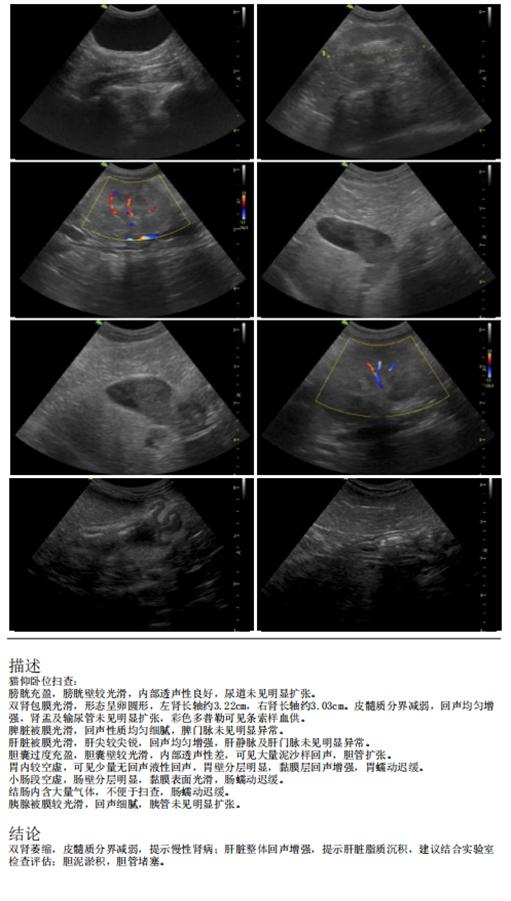

腹部彩超:

超声显示双肾萎缩,皮髓质分界减弱,提示慢性肾病;肝脏整体回声增强,提示肝脏脂质沉积;胆泥淤积,胆管堵塞。